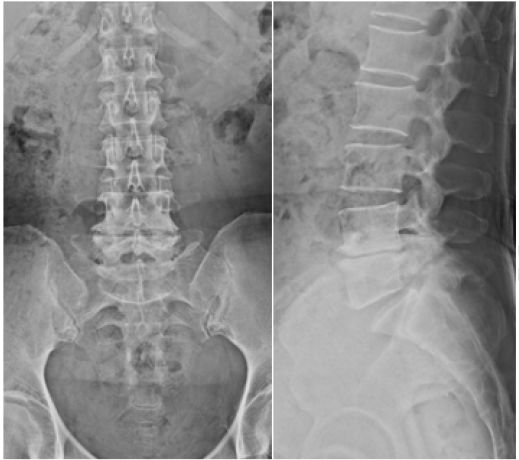

图1. X线平片显示L5-S1椎体峡部裂和I级腰椎滑脱,L4-L5椎间盘间隙减小。